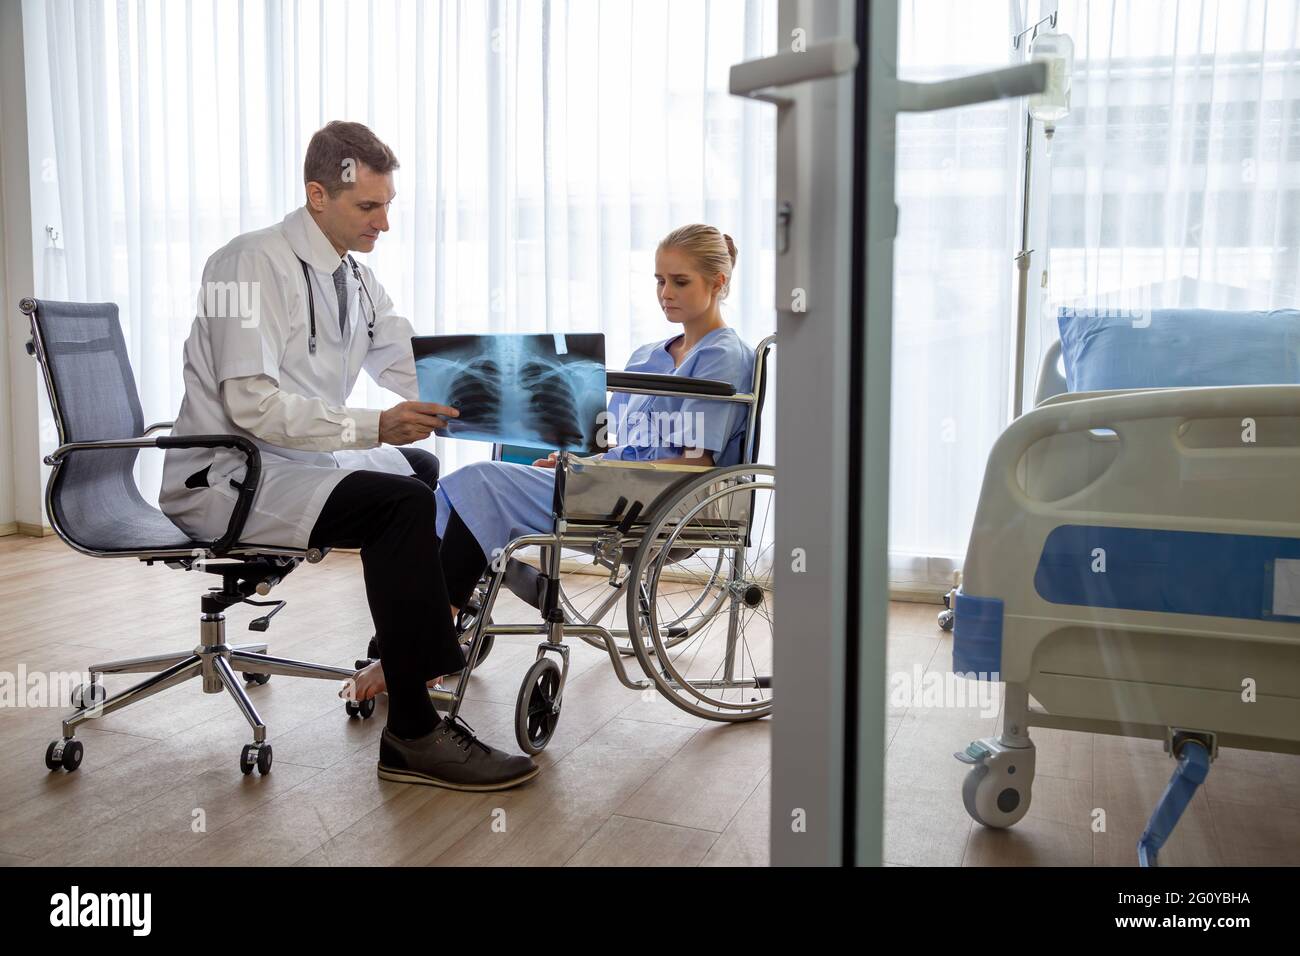

RF2G0YBGP–Médecin examinant le film radiographique thoracique de la patiente à l'hôpital. Concept de symptômes de syndrome respiratoire ou de pneumonie virale

RF2G0YBGW–Médecin examinant le film radiographique thoracique de la patiente à l'hôpital. Concept de symptômes de syndrome respiratoire ou de pneumonie virale

RF2G0YBHA–Médecin examinant le film radiographique thoracique de la patiente à l'hôpital. Concept de symptômes de syndrome respiratoire ou de pneumonie virale